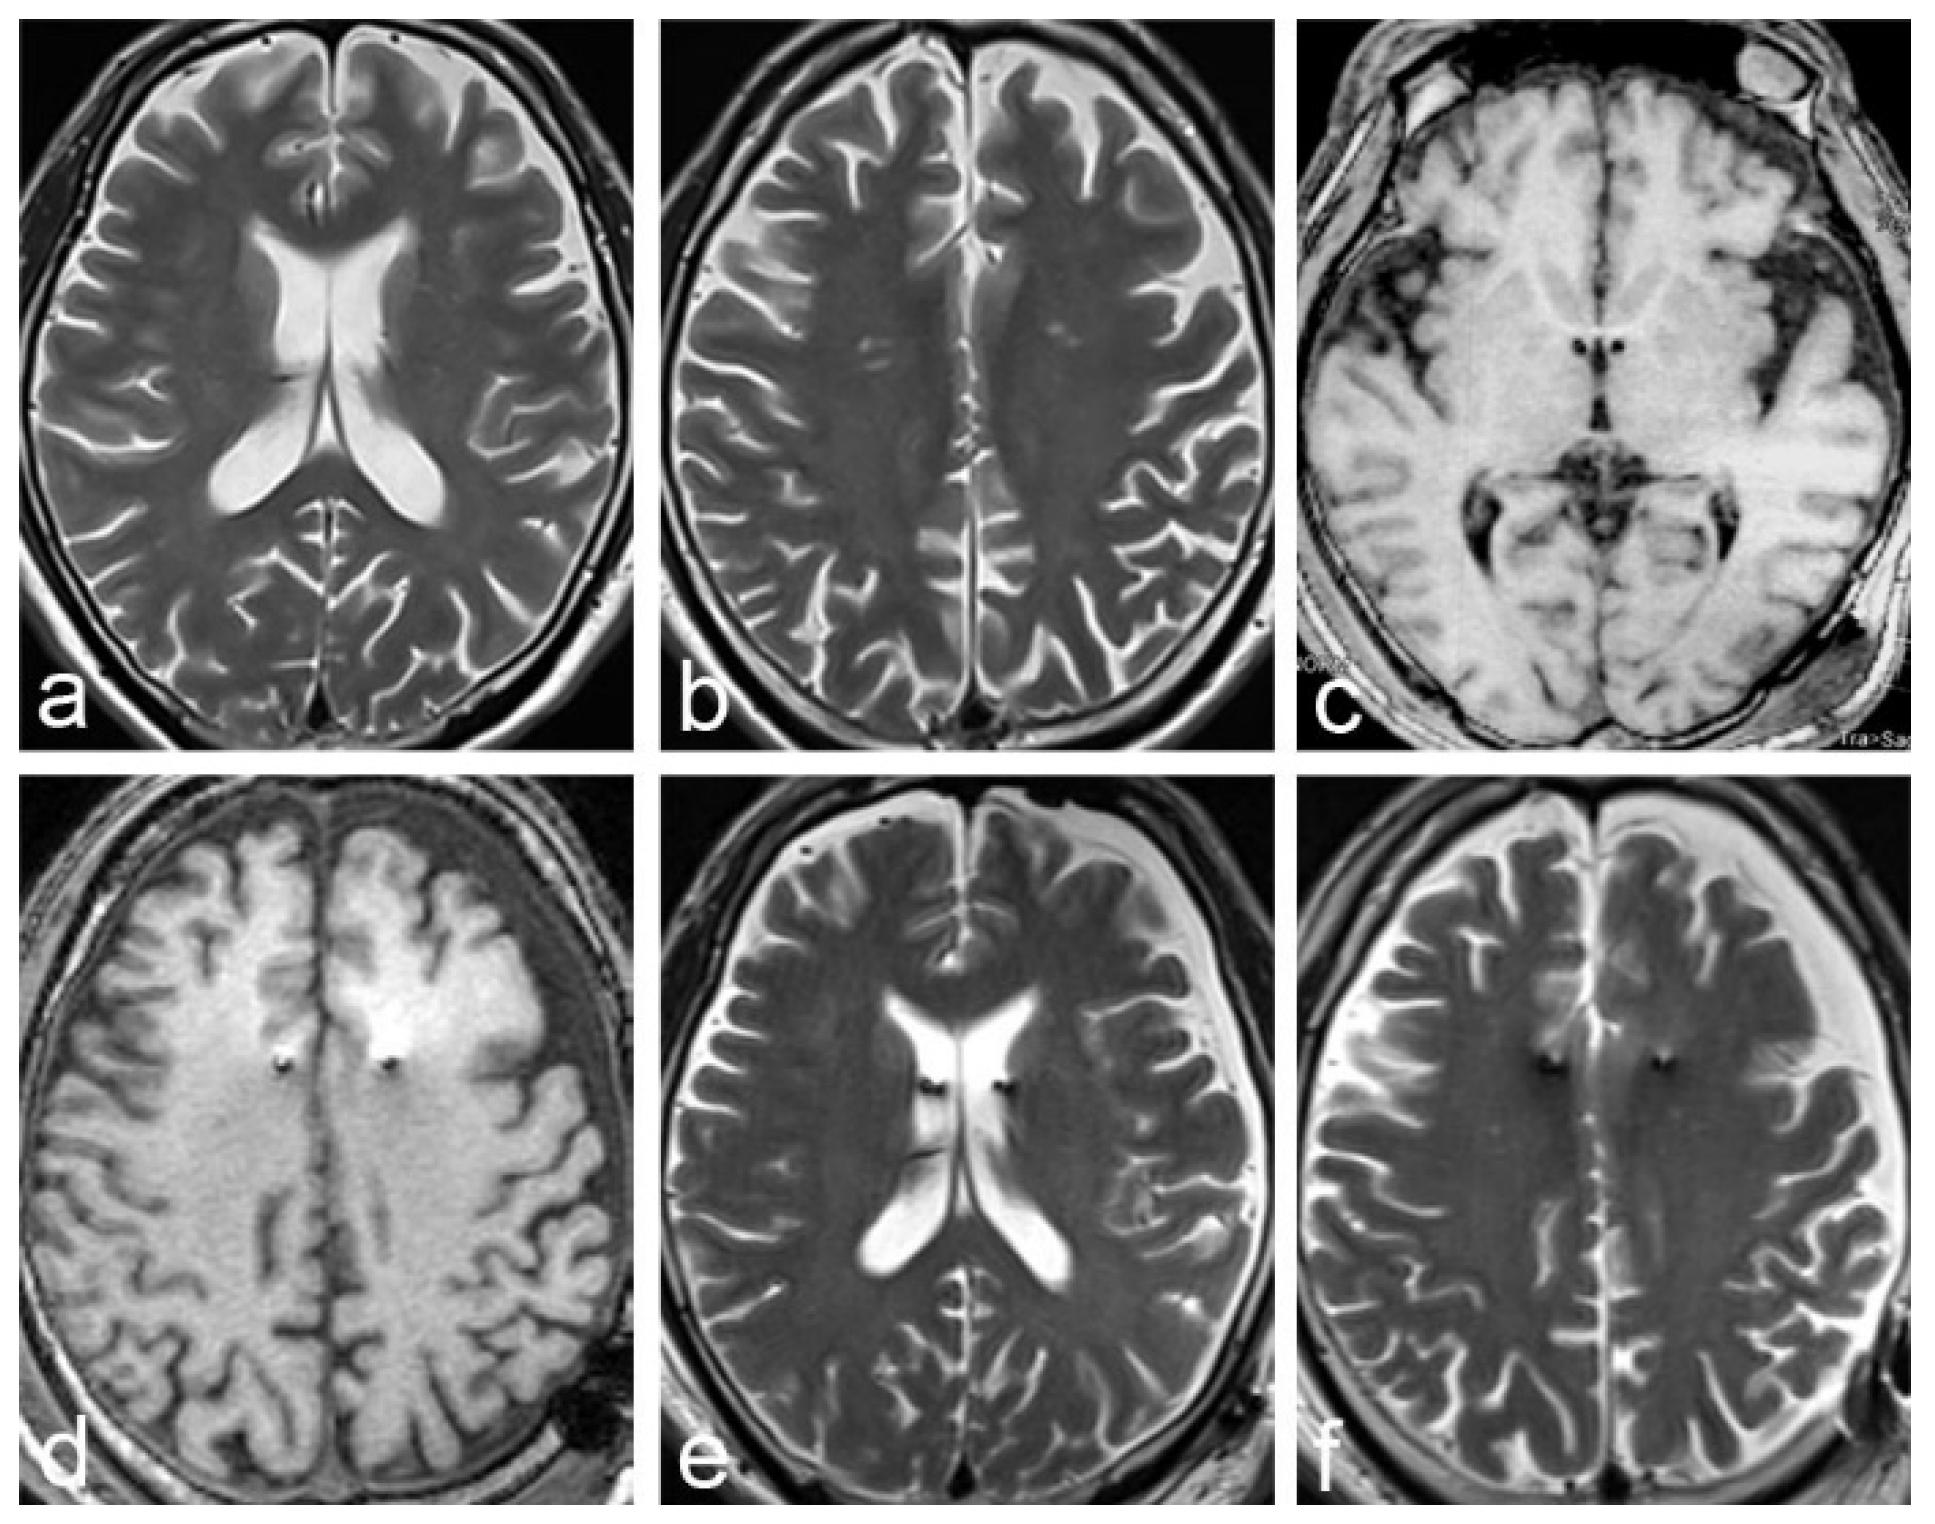

2.1. Case 1

2.2. Case 2

| Case 1 | 62 | F | Parkison’s disease | GPI | Yes | Yes | 36 days | description | poor |

| Case 2 | 56 | M | Alzheimer’s disease | fornix | Yes | Yes | 49 days | description | poor |